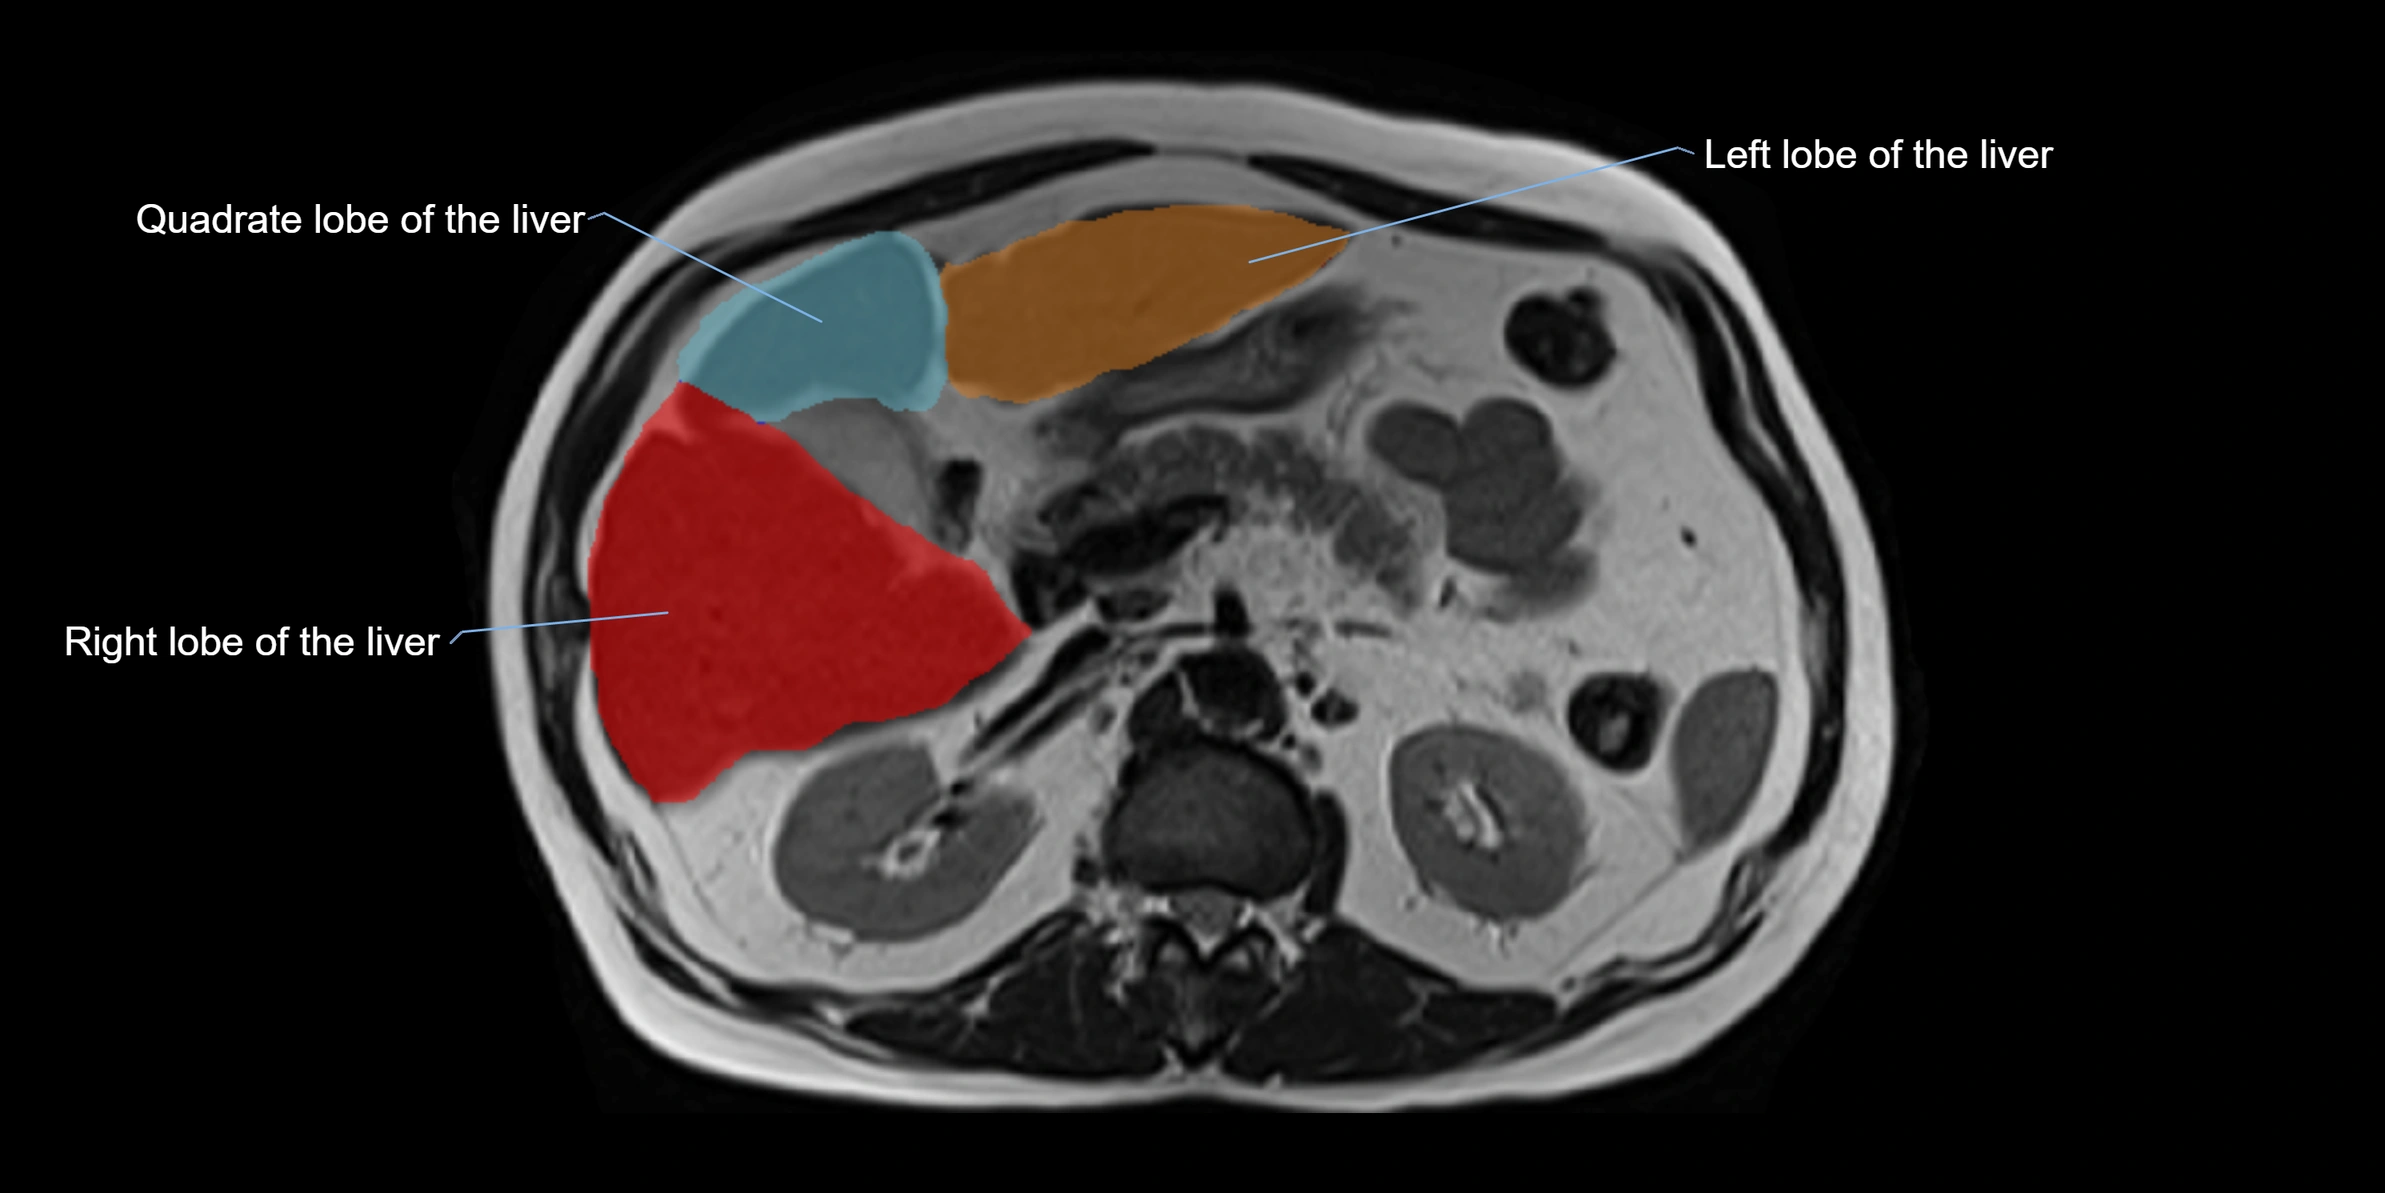

The caudate lobe of the liver is a distinct anatomical subdivision of the liver, designated as segment I in Couinaud’s classification. It lies on the posterior surface of the liver, between the fissure for the ligamentum venosum (left boundary) and the groove for the inferior vena cava (IVC) (right boundary). Superiorly, it is related to the posterior liver surface, and inferiorly it is separated from the left lobe by the porta hepatis.

This anatomical autonomy makes the caudate lobe especially significant in liver surgery, transplantation, and hepatic venous outflow obstruction syndromes (e.g., Budd–Chiari syndrome). Enlargement of the caudate lobe is a characteristic imaging feature in chronic liver disease and cirrhosis.

• Enlargement may be appreciated in cirrhosis or Budd–Chiari syndrome

• Homogeneous enhancement in the portal venous phase, similar to rest of liver

• Independent venous drainage into the IVC may be visualized